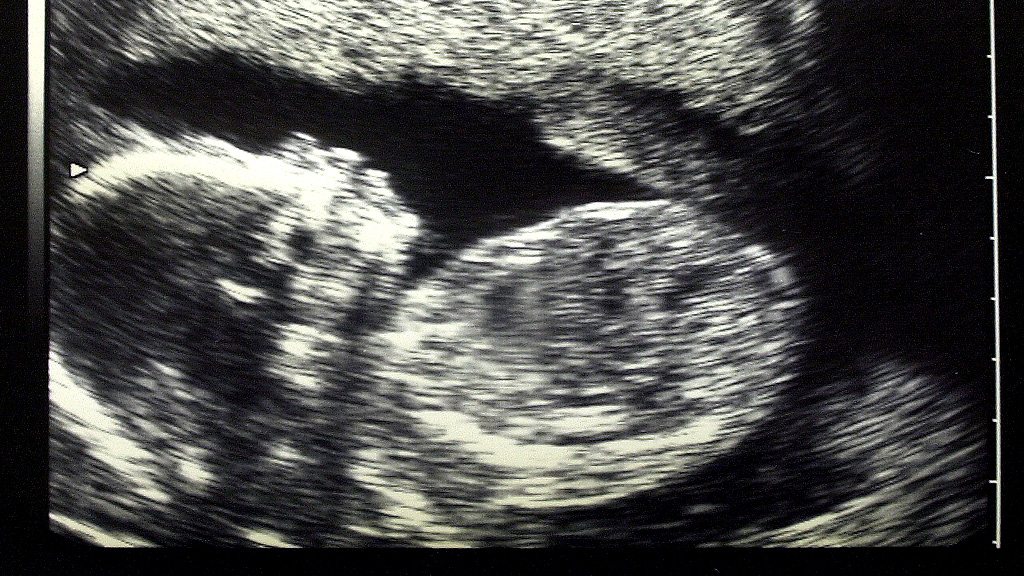

The nurture of intelligence begins in the womb